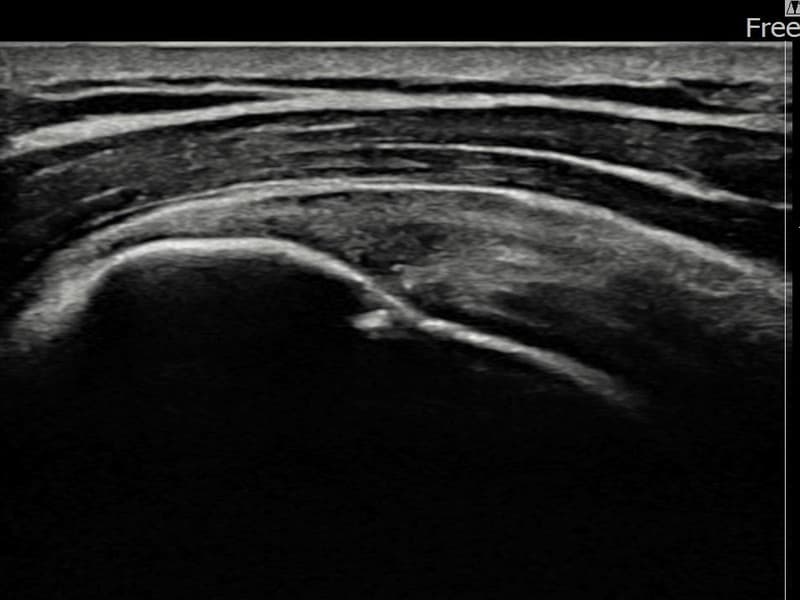

시술 전 초음파 측정 결과 파열 크기는 9mm × 4mm (힘줄 두께의 약 38% 결손)로 확인되었습니다. 시술 전 초음파에서 좌측 극상근건 부착부의 뚜렷한 에코 단절과 힘줄 결손 소견이 확인되었습니다. 시술 후 초음파에서 부착부 연속성이 회복되고 결손 부위에 재생 조직이 형성된 것이 관찰되었습니다.

60대 중반 남성 환자분으로, 왼쪽 어깨 통증이 6개월 이상 지속되어 내원하셨습니다. 은퇴 후 농작업을 하시면서 반복적으로 팔을 들어 올리는 동작을 많이 하셨고, 처음에는 무거운 것을 들 때만 아프다가 점점 팔을 조금만 들어도 통증이 심해지는 상태로 진행되었습니다. 초음파 검사에서 좌측 극상근건 부착부 부분파열이 확인되었으며, 초음파 유도 하 축소봉합술을 시행하였습니다. 시술 후 단계적 재활 운동을 통해 꾸준히 회복을 진행하였고, 시술 10주 후 추적 초음파에서 부착부 힘줄 연속성이 완전히 회복된 것이 확인되어 정상 생활에 복귀하셨습니다.